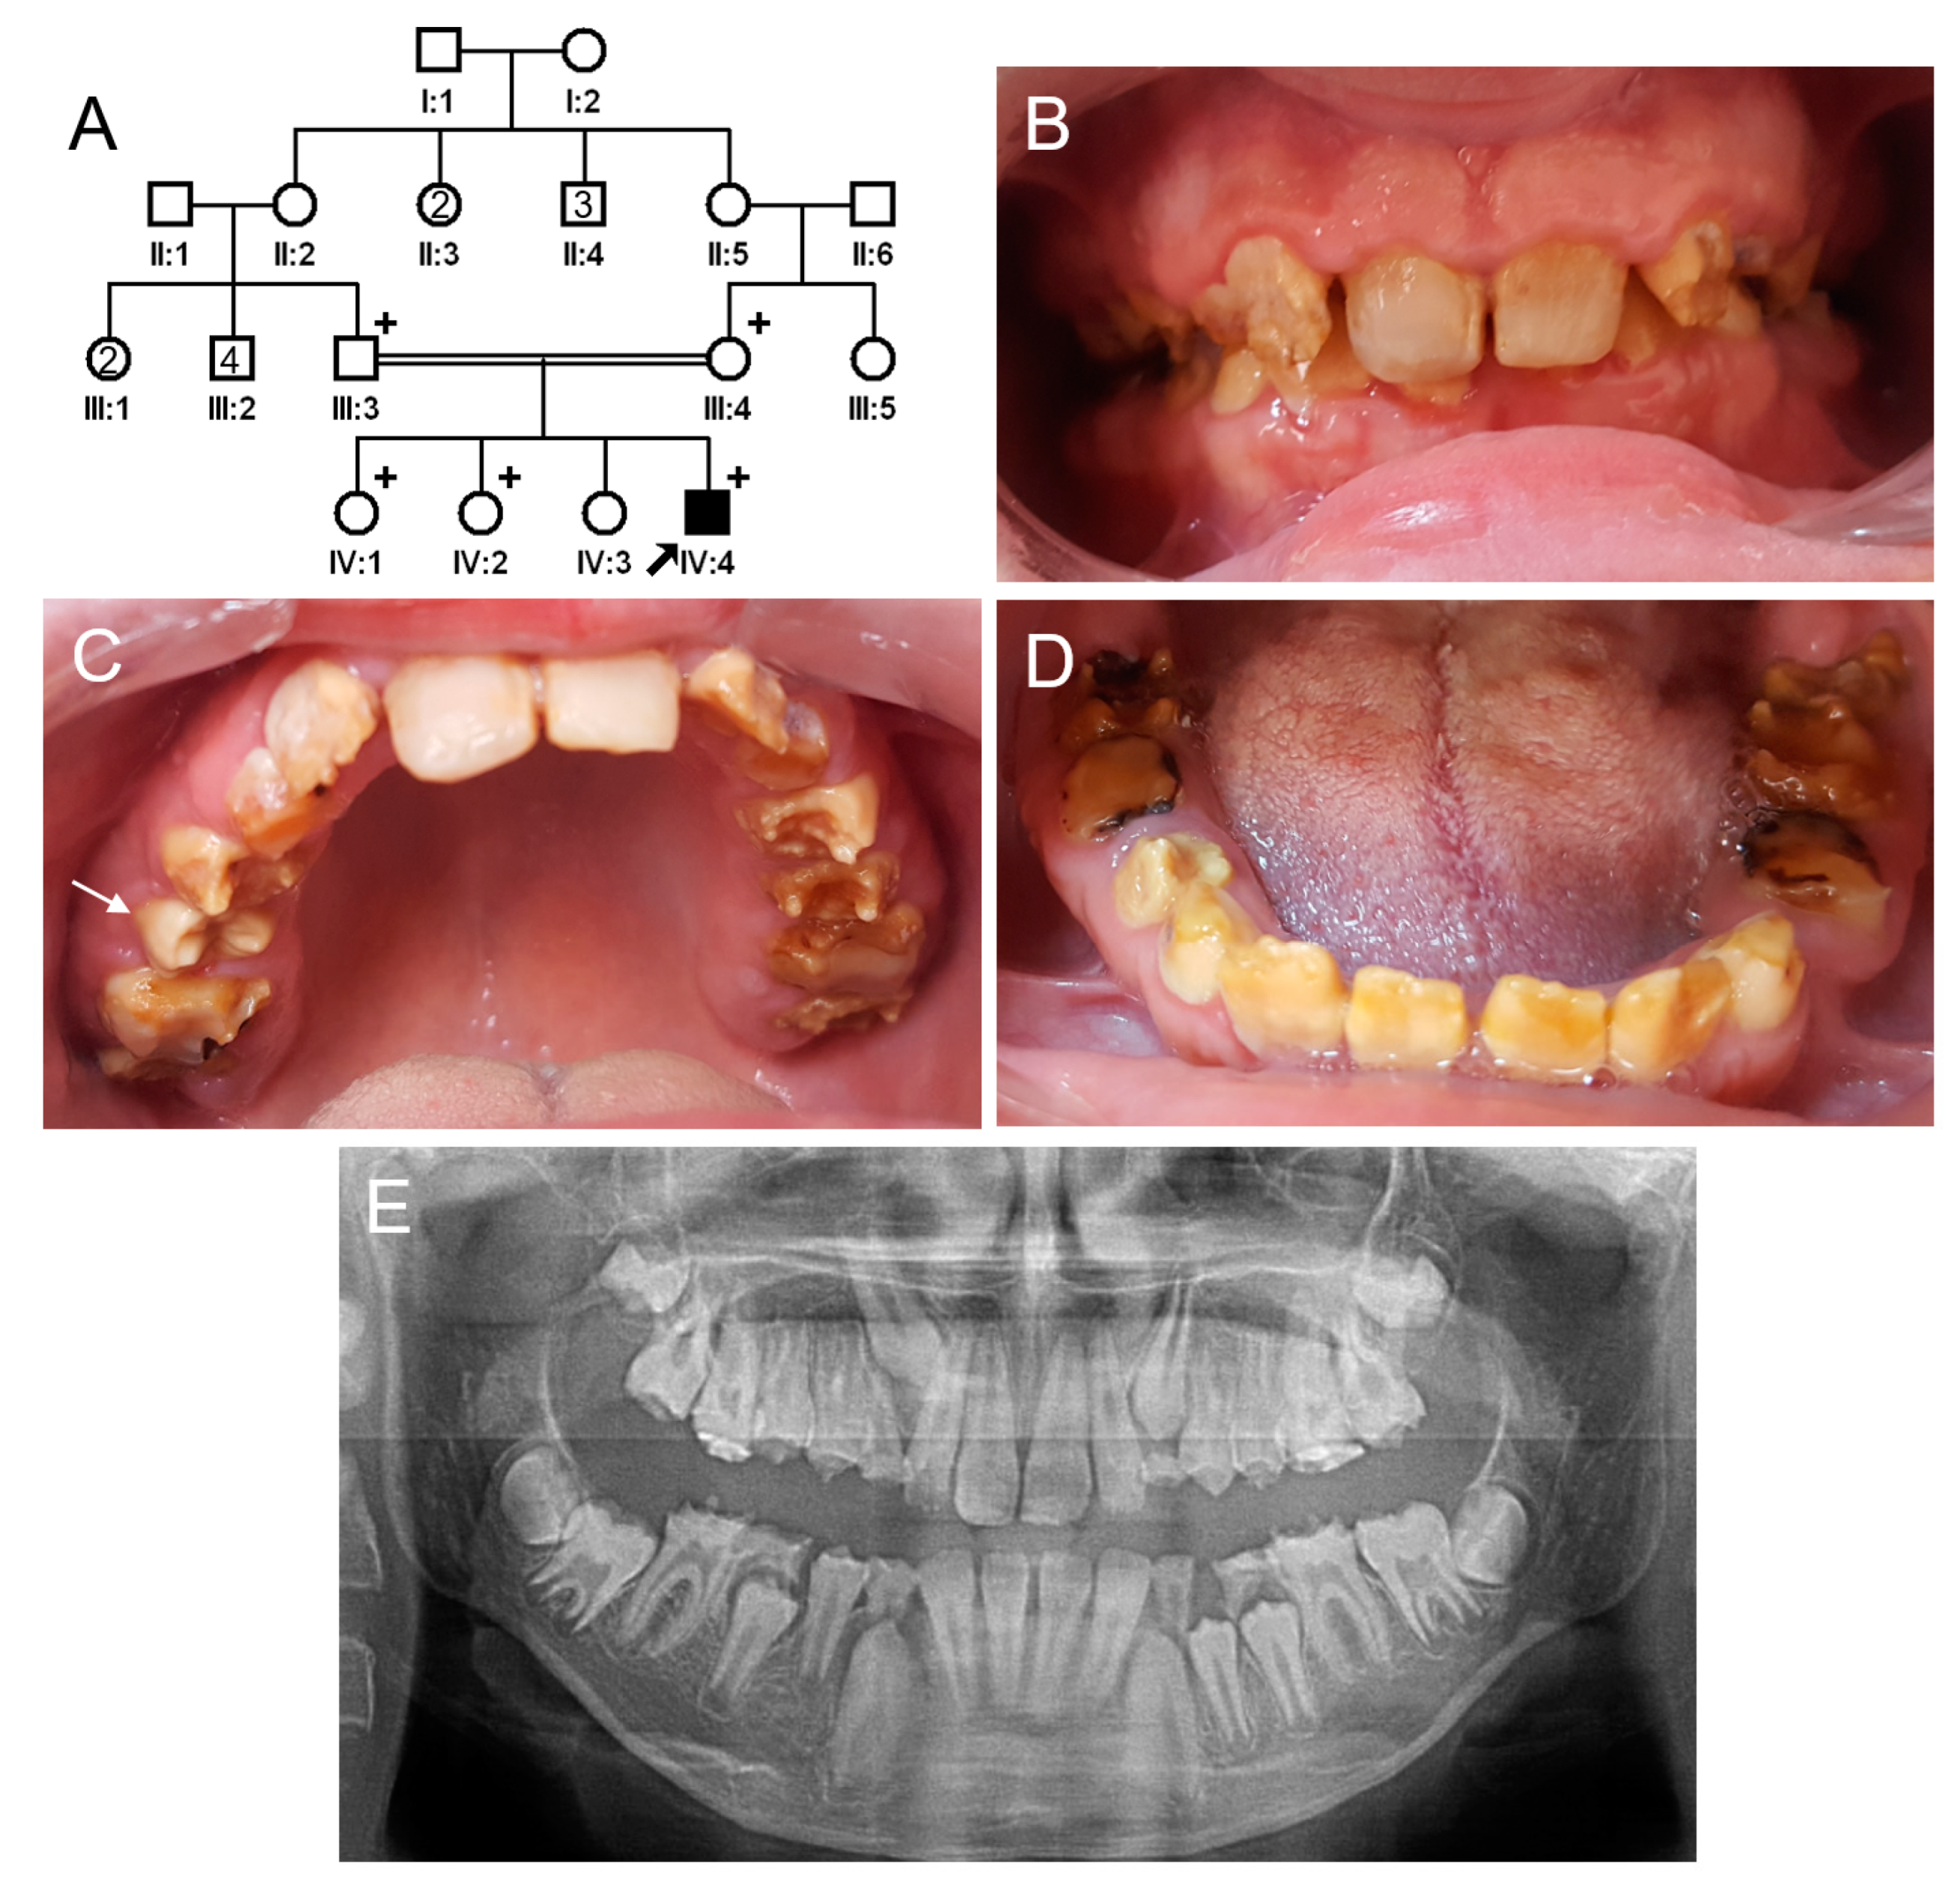

3.1. Family 1

The proband of family 1 was a 12-year-old male, the fourth child from a consanguineous Turkish family (Figure 1). Pregnancy and delivery were uneventful, and he had no remarkable past medical history. His primary and permanent dentitions exhibited characteristic features of hypomaturation amelogenesis imperfecta: generalized yellow-brown discoloration, normal or near-normal thickness of enamel before tooth eruption, rapid dental attrition, or enamel fractures due to weak enamel. He also exhibited class II malocclusion with a deep overbite. There were no other family members with a similar dental phenotype. A recessive or de novo dominant mutation, therefore, was suspected.

Figure 1.

Pedigree, clinical photos, and panoramic radiograph of family 1. (A) Pedigree of family 1. The black symbol indicates the affected individual, and the proband is indicated by a black arrow. Plus signs above the symbols indicate participating individuals. The number inside the symbol indicates the number of siblings with the same gender. (B–D) Clinical photos of the proband at age 12 years. Maxillary central incisors have been treated with direct composite resin restorations. A newly erupted tooth (white arrow) exhibits a normal shape but discoloration before enamel fracture or attrition. Otherwise, all affected teeth show yellow-brown discoloration and enamel fractures and accelerated attritions. (E) Panoramic radiograph of the proband at age 12 years. Radiographically, unerupted teeth show normal crown shape with a reduced enamel radiodensity. Severe attrition and fractures can be seen in some teeth, especially in the first molars and deciduous second molars.